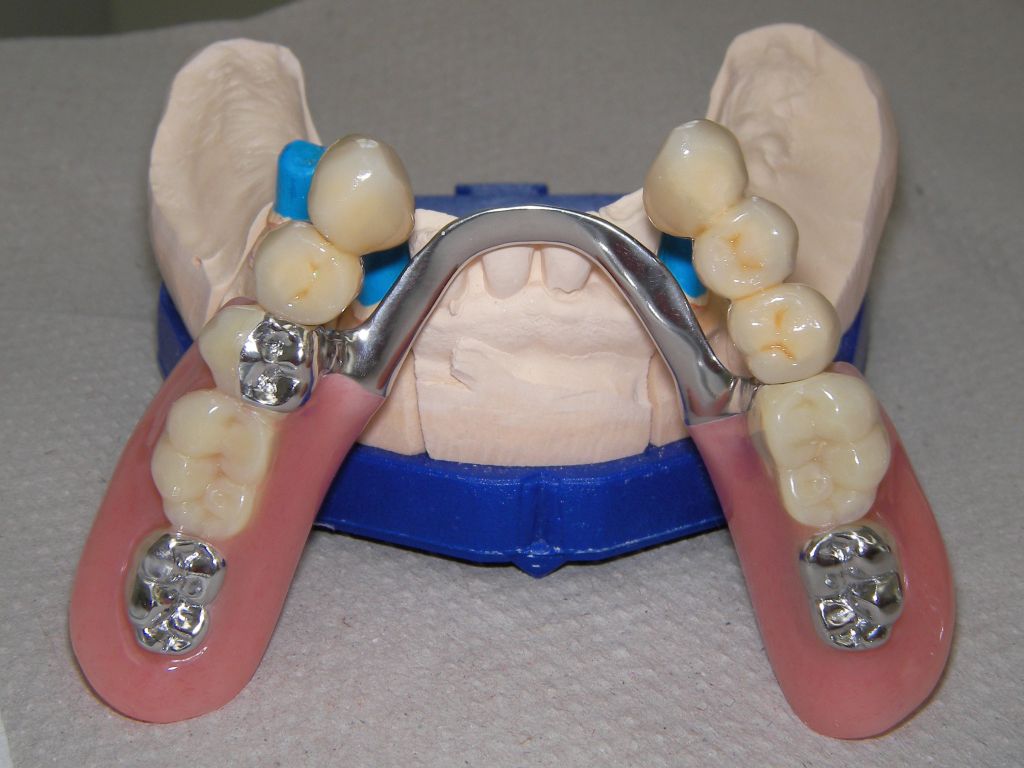

Links Bilder des Oberkiefers, rechts des Unterkiefers. Die Arbeit wurde von dem Dentallabor "Heitmeyer Zahntechnik", Osnabrück, gefertigt. Dem Labor ist hier für die hervorragende Arbeit zu danken, dem Patienten für die Freigabe der Bilder! |

Die Unterseite, die später der Mundschleimhaut aufliegt, ist im Bereich der Druckknöpfe hochglanzpoliert und damit gut pflegbar, was wichtig für gesundes Zahnfleisch an diesen Stellen ist. Das Kugelattachment (Druckknopf) ist das Preci-Clix (Fa. Ceka). |

Die Zähne auf der Prothese sind aus verarbeitungstechnischen Gründen auch heute meist noch aus Kunststoff, auch wenn teurere Keramikzähne möglich wären. Kunststoff verschleißt über die Jahre, der Biß verändert sich. Um letzteres zu verhindern, sind hier zusätzlich Metallkauflächen eingearbeitet, die sich nicht verändern werden. Auch Verbindungselemente verschleißen. Um den Verschleiß reparieren zu können, sollte der Verschleiß aus dem Mund in die Prothese gelenkt werden. Im Mund deshalb hier 4 harte Titankugeln, die passenden Druckknöpfe in der Prothese aus Kunststoff, wo sie leicht ausgewechselt werden können. | |

Hier das vorläufig letzte Bild dieses Falles mit maximaler Lippenöffnung einige Tage nach Eingliederung von Kronen und Prothesen bei der Nachkontrolle (Ende März 2006). Bislang lief, von einigen anfänglichen Prothesendruckstellen abgesehen, die aber leicht behoben werden konnten, alles glatt. Die Heiß-/Kaltempfindlichkeiten an den beschliffenen Zähnen, die häufig auftreten, waren nach der Zementierung der Kronen verschwunden. Die eigentliche prothetische Behandlung dauerte vom 22.2.06 bis zum 20.3.2006 (nur 5 Sitzungen), also 4 Wochen und war damit recht zügig. Ähnliche Fälle können auch 6 Wochen dauern. |